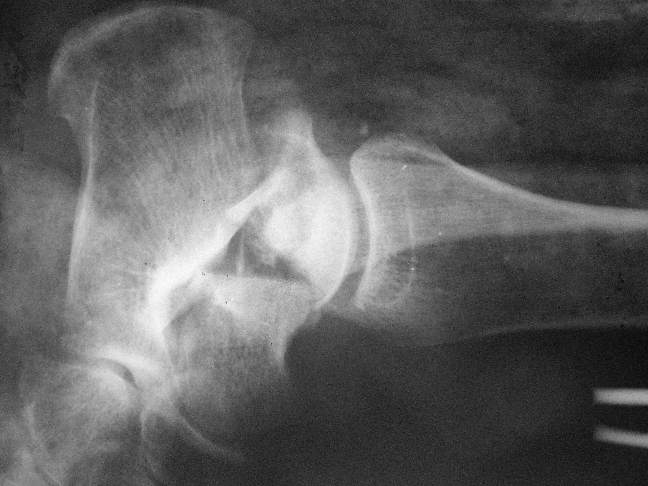

Планируем провести повторную репозицию и фиксацию винтами.

1. Закрытая репозиция рентгенконтоль интраоперационный (аппарат Арман) и

фиксация из заднее-наружного доступа.

2. При неудачной закрытой репозиции переходим на открытое вправление двумя

доступами медиальным и латеральным "по ходу оси таранной кости" и через

дополнительный задний доступ вводим винты кортикальные 4,5 мм или  3,5 мм

3. после открытой репозиции фиксация двумя винтами через боковые доступы

погружая их под суставную поверхность